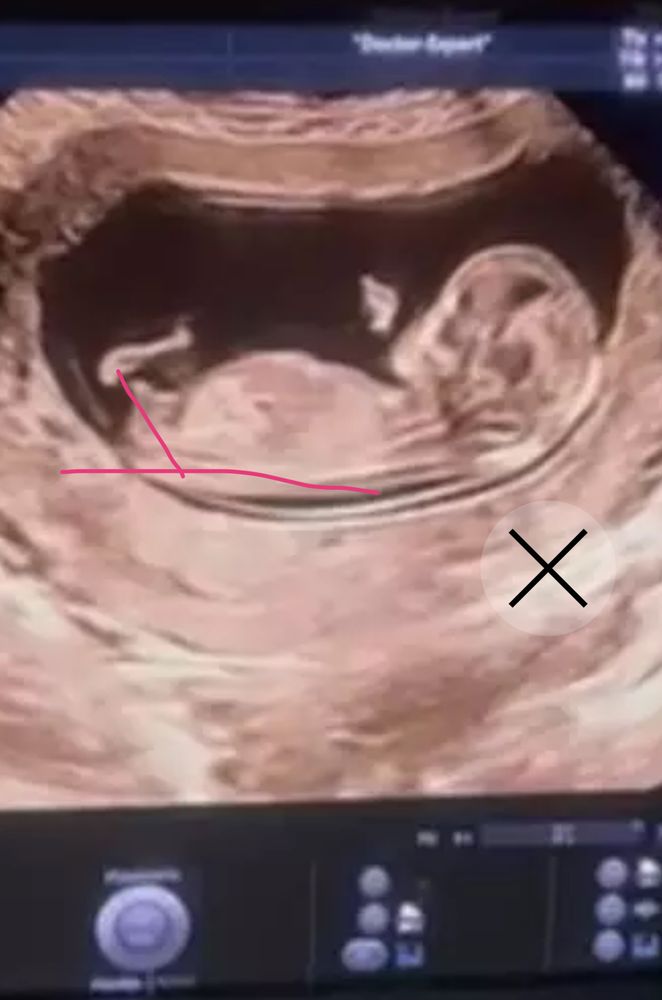

УЗИПредположительно по узи в 12 недель и 2 дня мальчик,может быть девочка?у кого так было?

Best mammy , тут классический угол , бугорок торчит вверх, даже сомнений нет, что это мальчик

С 95% вероятностью мальчик. Малыш у вас хорошо лег, угол классический, у него бугорок торчит вверх, это мальчик скорее всего.